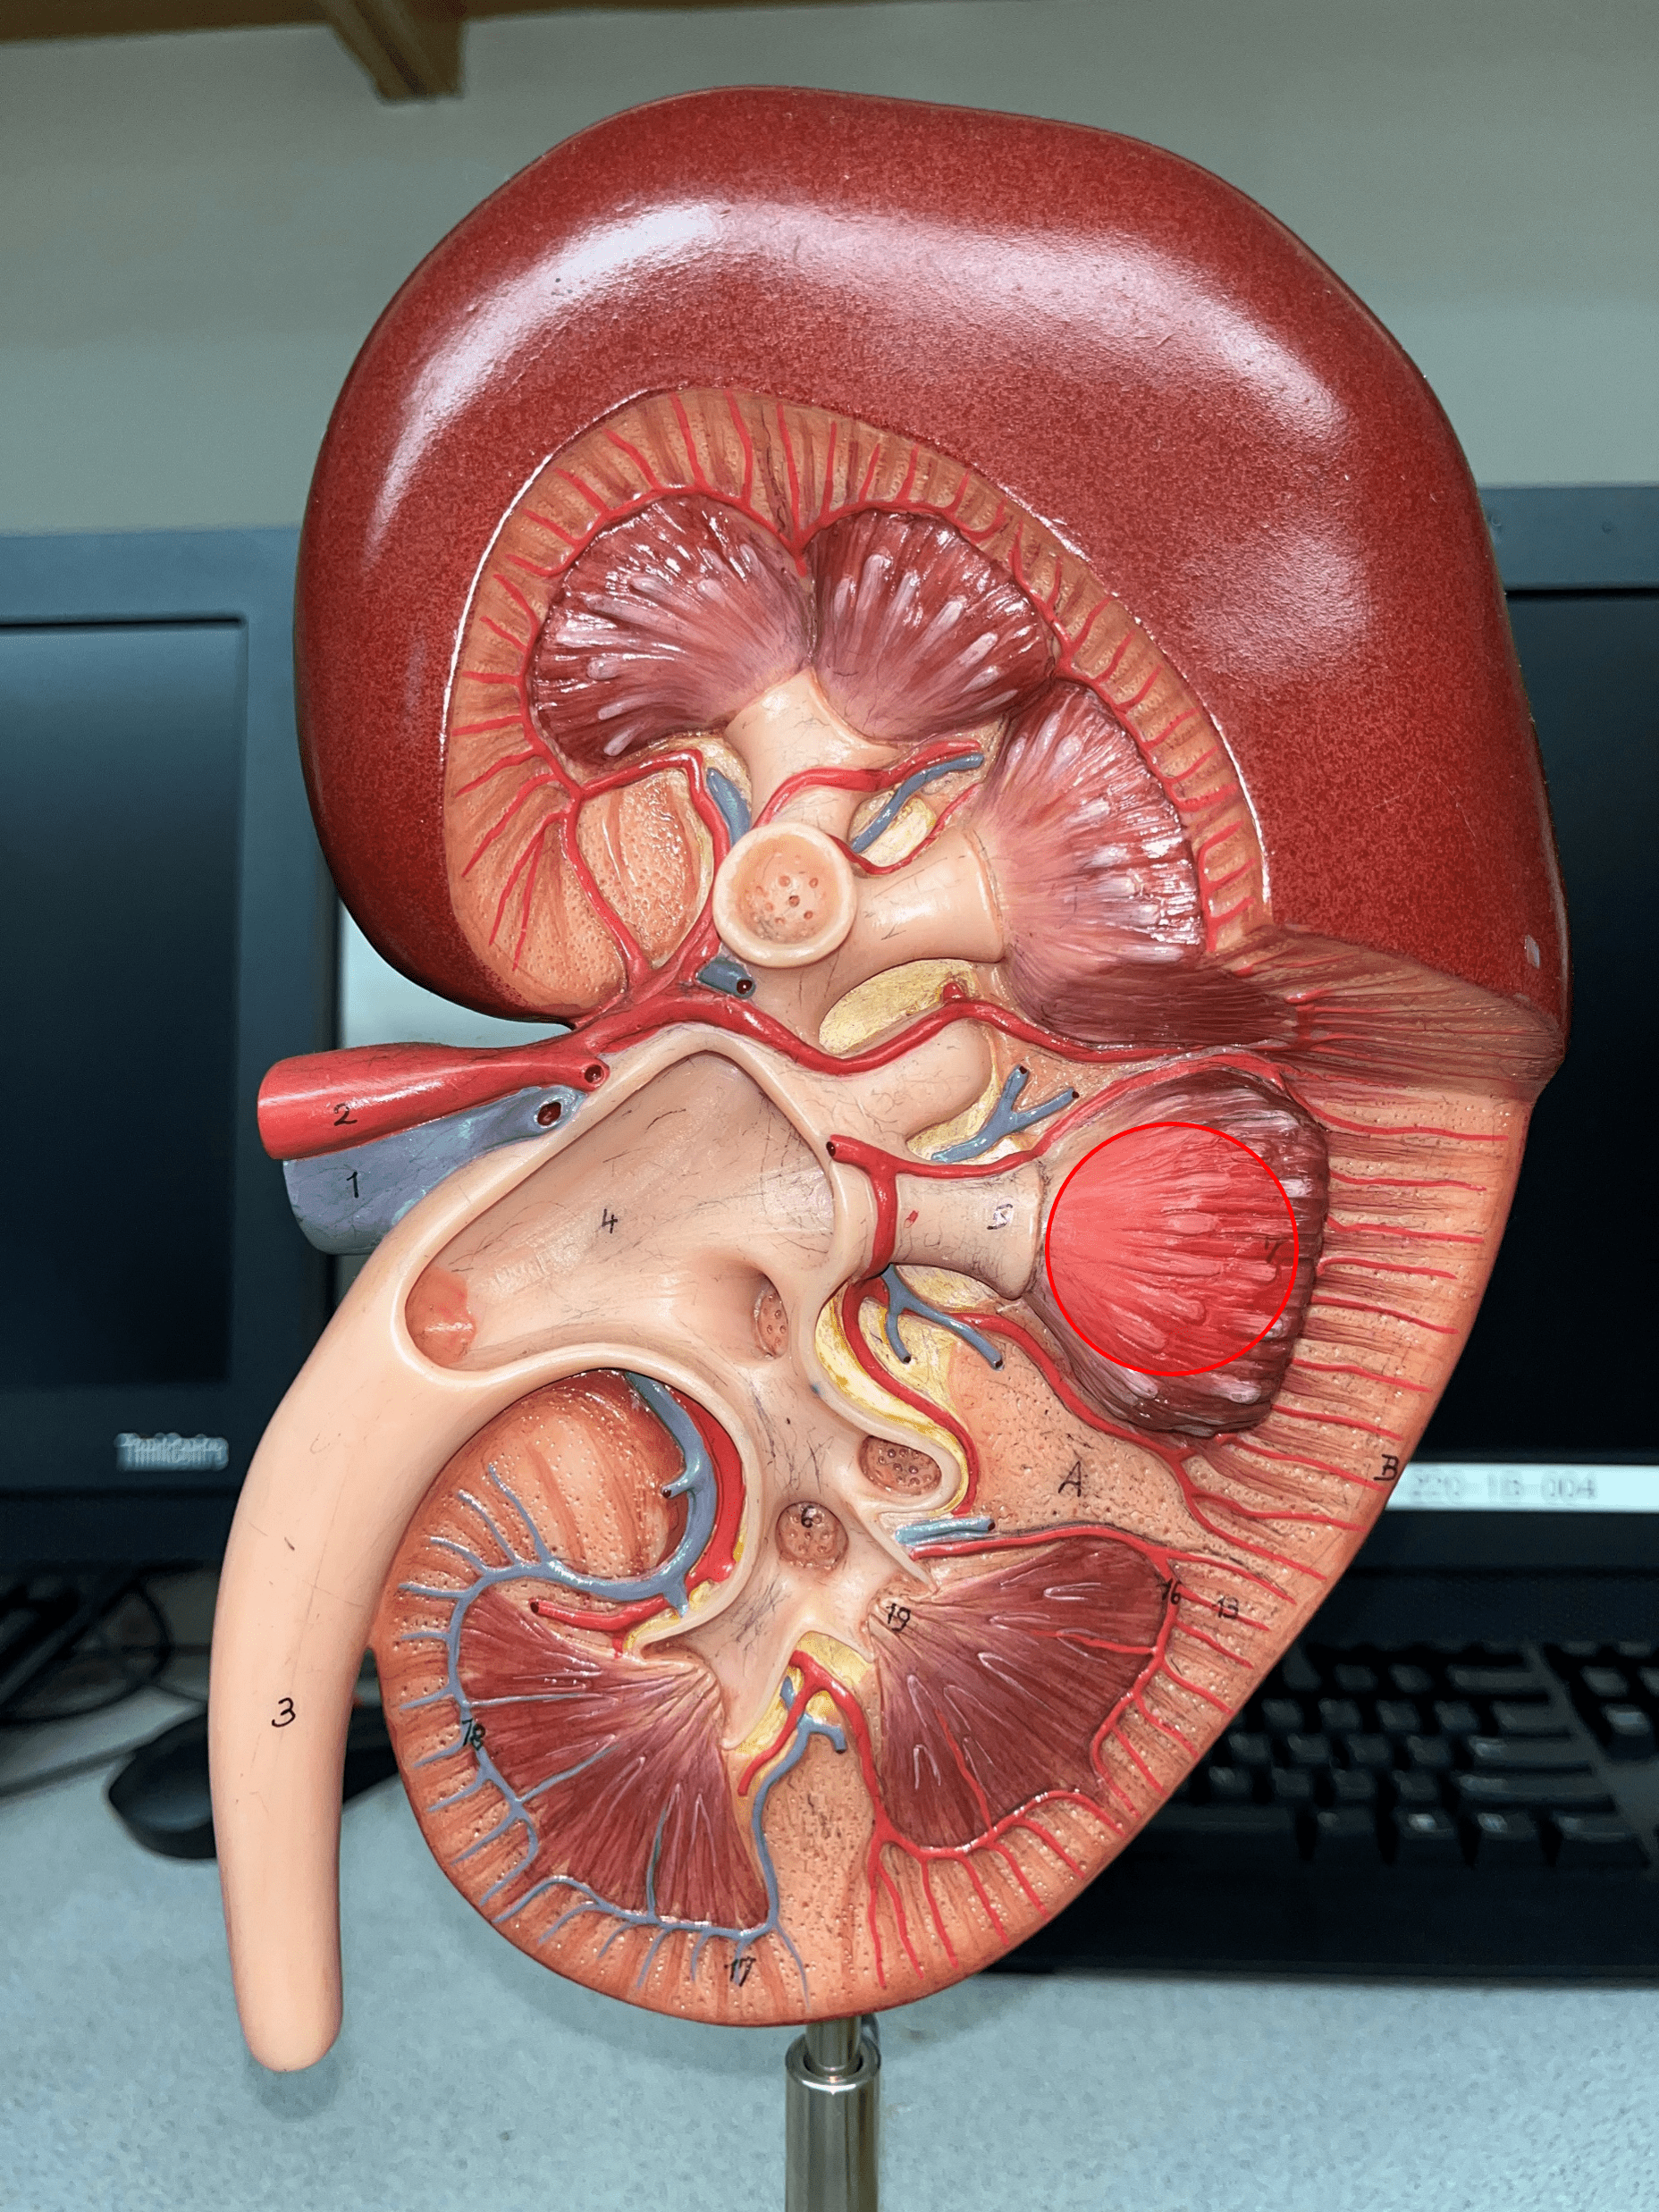

renal pyramid

• A triangular structure found in the renal medulla.

• The base faces the renal cortex.

• The renal papilla (apex) faces the renal pelvis.

• The base faces the renal cortex.

• The renal papilla (apex) faces the renal pelvis.

renal papilla

The apex of the renal pyramid facing the renal pelvis.

minor calyx

• A cup-like extension that collect urine from the renal papilla.

• Converges with others to form a larger major calyx.

• Converges with others to form a larger major calyx.

major calyx

• The convergence of several minor calyces.

• Drains into the renal pelvis.

• Drains into the renal pelvis.